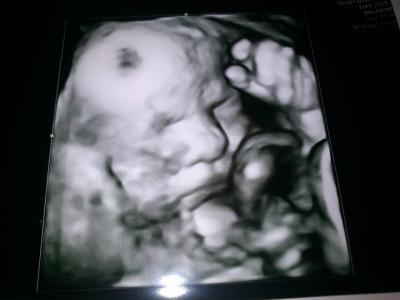

So weit alles in Ordnung ;) der Kleine Mann heute 30+3 Wiegt ca. 1595 Gramm und ist 42cm groß ansonsten ist sie sehr zufrieden mit der Entwicklung des kleinen haben heute auch wieder Ultraschall gemacht und ein ganz tolles Bild mitbekommen.

Bild zu Termin heute :) - Forum für Mai - Mamis